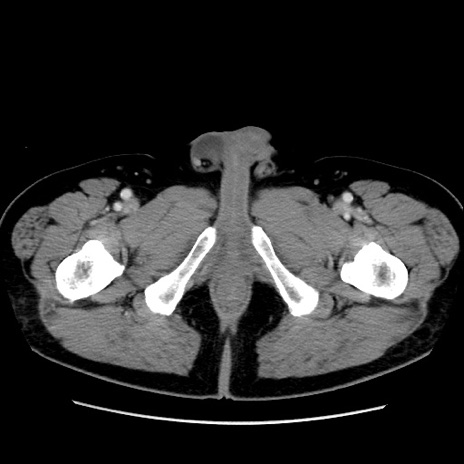

冠状断像